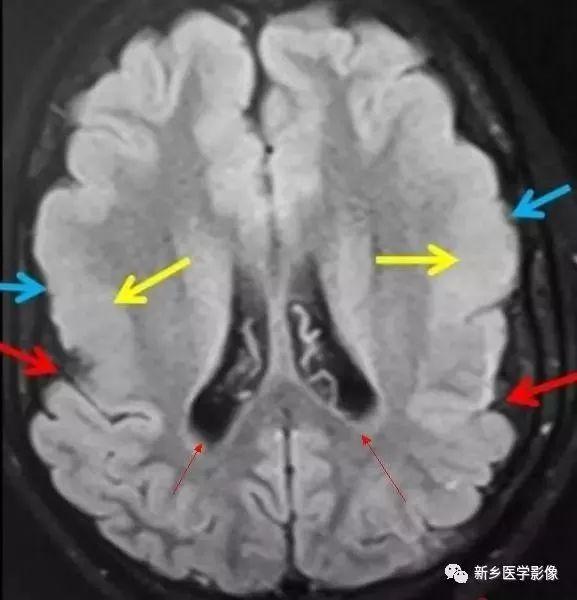

(3)无脑回和巨脑回

无脑回和巨脑回是一组因神经元移行异常所致的脑回发育异常。巨脑回也称平滑脑。巨脑回指有部分脑回存在,这些脑回异常增大增宽.脑沟变浅。巨脑回主要位于额、颞部。无脑回上要位于顶、枕部。

临床上,无脑回和巨脑回畸形患儿均表现有小头畸形和轻微的面部异常,完全无脑回畸形常在两岁前死亡.不完全无脑回畸形存活常能长期。

CT和MR均能够很好显示无脑回和巨脑回畸,表现为大脑半球表面几乎呈光滑状,仅可见少数宽阔、粗大、平坦的脑回,脑沟缺如.脑灰质增厚,脑白质变薄,灰白质分界面异常平滑,见不到白质向灰质内伸入的现象。常见透明中隔腔存在.侧脑室扩大,蛛网膜下腔增宽。